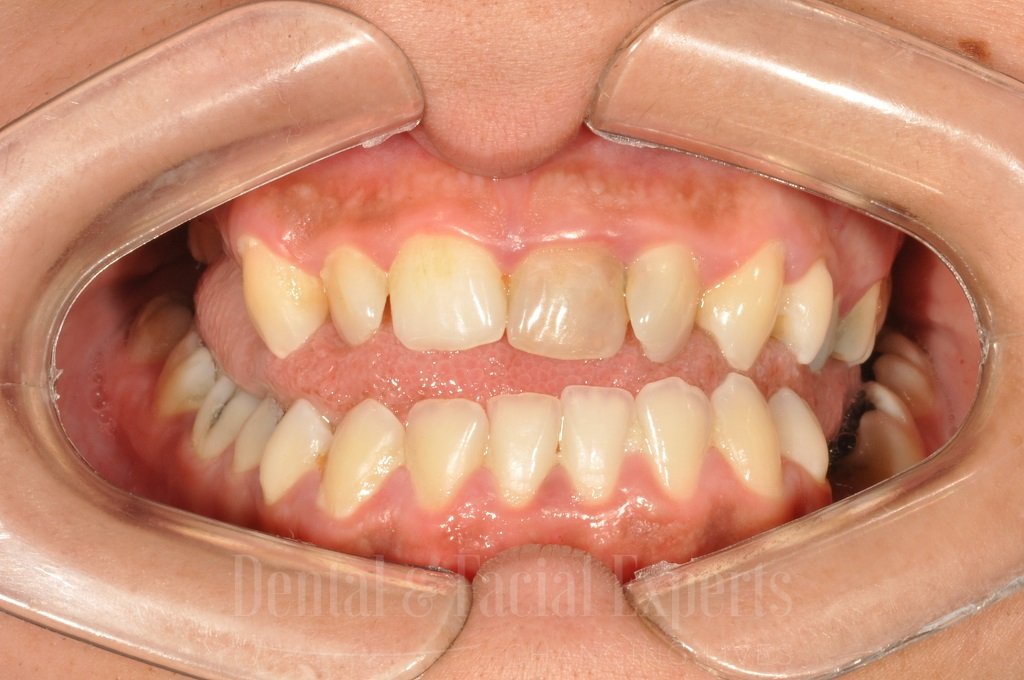

La cirugía maxilofacial es una especialidad médico-quirúrgica que aborda patologías, malformaciones y traumatismos de la cara, mandíbula, maxilares, boca y cuello. Su objetivo es restaurar la funcionalidad y mejorar la estética facial, abarcando procedimientos tanto reconstructivos como cosméticos.

La cirugía estética del esqueleto facial permite modificar de forma precisa la estructura ósea del rostro para lograr una armonía facial equilibrada y duradera. Mediante técnicas avanzadas, como osteotomías y remodelación de pómulos, mentón o mandíbula, es posible corregir desproporciones, mejorar el perfil facial y reforzar la simetría. En Clínica Verbauvede, el Dr. Fernando Gómez combina su experiencia en cirugía maxilofacial y estética para ofrecer resultados naturales, seguros y adaptados a las características de cada paciente.